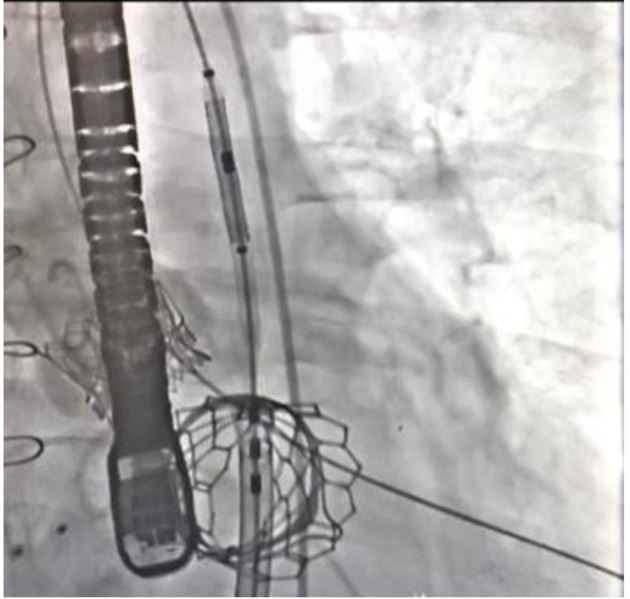

In the next step, a 6-French MP-1 guide catheter was passed over J-wire into the left atrium. Once the guide catheter was in the left atrium, a GooseNeck 20-mm snare was passed and manipulated to snare the Glidewire. Then, a 16-French Edwards TAVR sheath was passed over the Glidewire into the inferior vena cava (IVC). The sheath was advanced over the interatrial septum after an atrial septostomy was performed using a 7-mm Mustang balloon. The 29-mm Edwards Sapien S3 valve was passed through the sheath across the mitral valve bioprosthesis. After multiple coplanar views obtained of the mitral valve, ventilation was held and rapid pacing was initiated and the valve was deployed (Fig. 2). Echocardiographic finding did not demonstrate any perivalvular leak.

Figure 2.

Balloon inflation and transcatheter bioprosthetic mitral valve deployment.